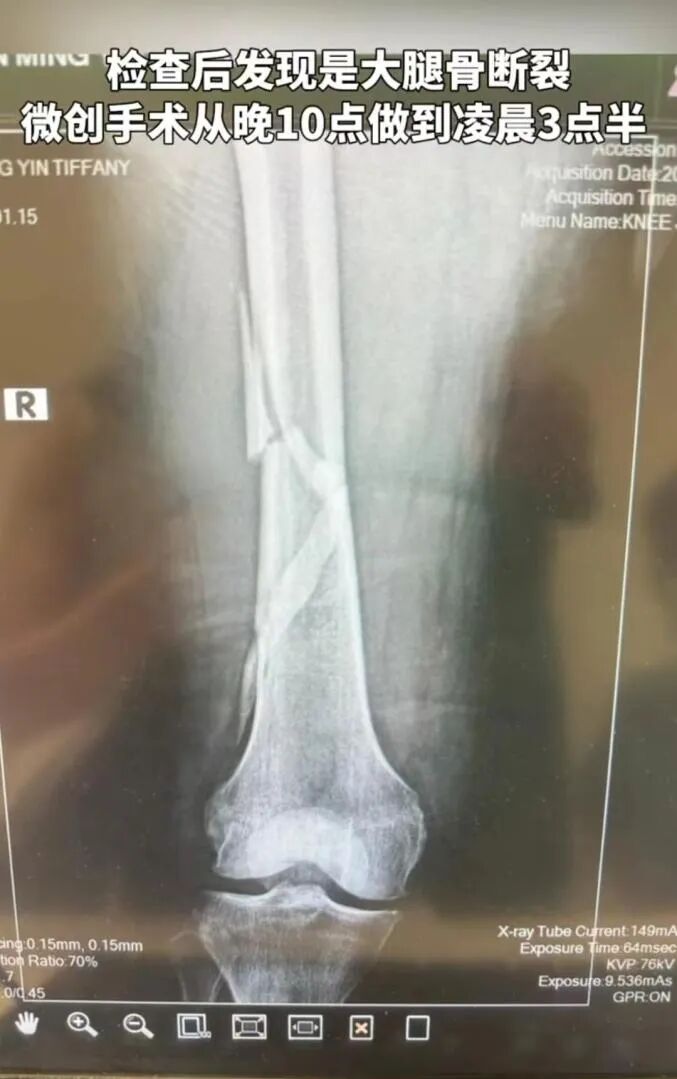

4月26日,向华强夫人陈岚在短视频平台上发文称自己大腿骨断裂。视频中,能看到向太全身被包裹住,躺在担架上,从救护车上被医护人员小心翼翼地推下来。她的丈夫向华强一直跟随,满脸担忧。

陈岚通过文字讲述了整个过程。她称,前几天在浴室洗澡时,在刚好没有防滑垫的地方摔倒了,“当时整个人都是懵的,痛到站不起来。”虽然有呼救,但因为洗澡前关了浴室门,所以在呼喊了半个小时后,才被听到。当时,陈岚准备叫救护车,但担心救护车到家里会引起不必要的猜测,于是第一晚她在浴室里没有动,直到第二天早上才叫了私人医生。

到医院后,通过专业检查,发现她大腿骨断裂,于是做了手术。“整个过程我没流一滴眼泪。现在大腿里有一根很长的钛金属管和四根髓钉。”